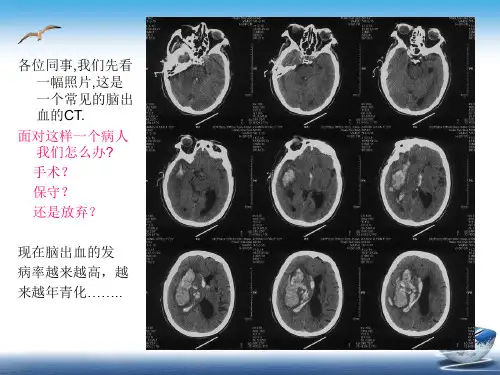

高血压脑出血的外科治疗

高血压脑出血的相关问题

高血压脑出血的诊断问题:

高血压

脑出血:出血的部位 鉴别:血管畸形,动脉瘤,血管淀粉样变等导致的